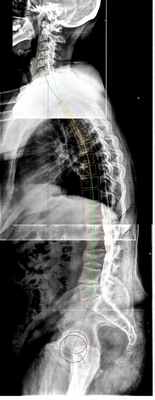

Рис 3. Оценка сагиттального баланса позвоночника. На представленных снимках видна посттравматическая кифотическая деформация поясничного отдела позвоночника, ретроверсия таза, грудной гиперкифоз, нарушение глобального сагиттального баланса.